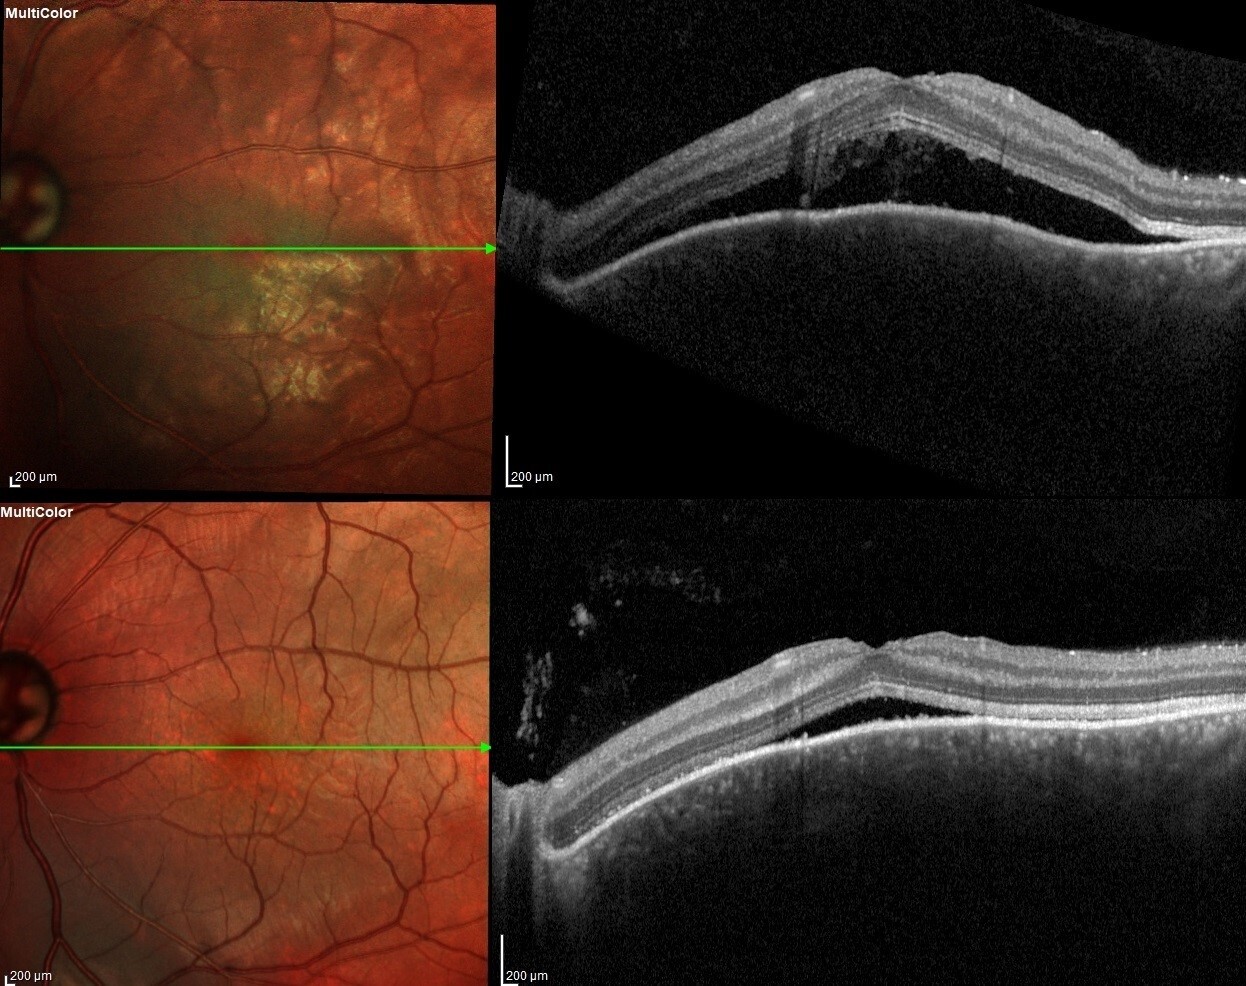

РЕЗУЛЬТАТЫ. На первые сутки после операции на левом глазу выявлено: гипотония, измельчение передней камеры, серозная цилиохориоидальная отслойка. Проведена задняя трепанация склеры, восстановлен объем передней камеры вискоэластиком. На следующие сутки нормализация ВГД и полное прилегание сосудистой оболочки, но обнаружена отслойка нейроэпителия в макулярной области, в связи назначены инъекции глюкокортикостероидов с положительным эффектом. Через 1 месяц после операции жалобы отсутствуют, оболочки прилежат, на левом глазу ВГД - 16 мм рт. ст. без гипотензивных капель, острота зрения на оба глаза 1,0.